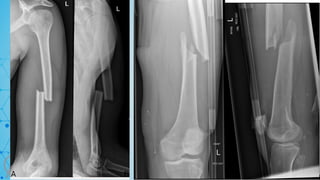

CLASSIFICATION

• Bone = 3

• Segment = 3

• Type = C

• Group = 3

• 33-c3

• Segment = 2

• Type = A

• 32-A3